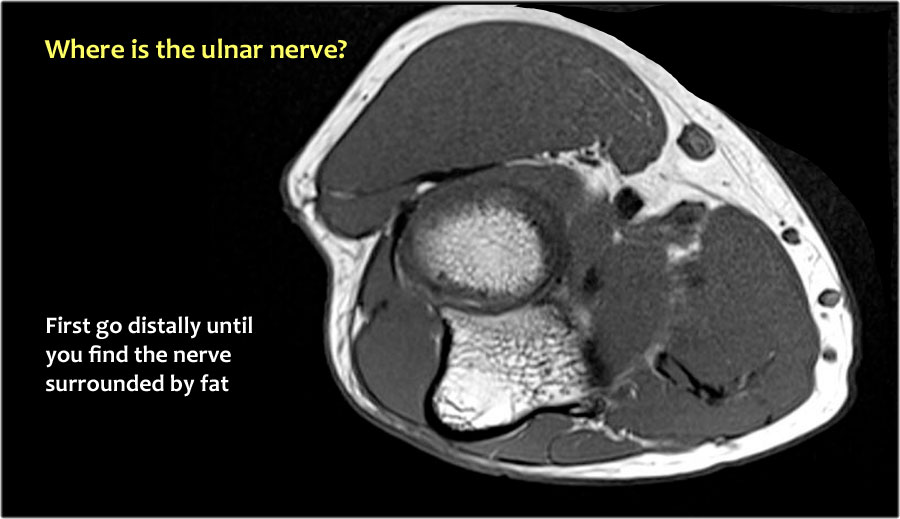

Vì vậy, khi chúng ta quay lại hình ảnh, bạn sẽ nhận thấy rằng có thể khó tìm thấy dây thần kinh.

Bất kỳ cấu trúc dưới da nào trong số này đều có thể là dây thần kinh đã được chuyển vị.

Một cách để thực hiện là đi theo các cấu trúc về phía xa cho đến khi tìm thấy dây thần kinh trụ ở phía xa tại vị trí bình thường của nó ở vùng cẳng tay gần được bao quanh bởi mô mỡ.

Sau đó khi bạn theo dõi nó về phía gần, bạn sẽ nhận thấy rằng đây là một trường hợp chuyển vị dưới da.